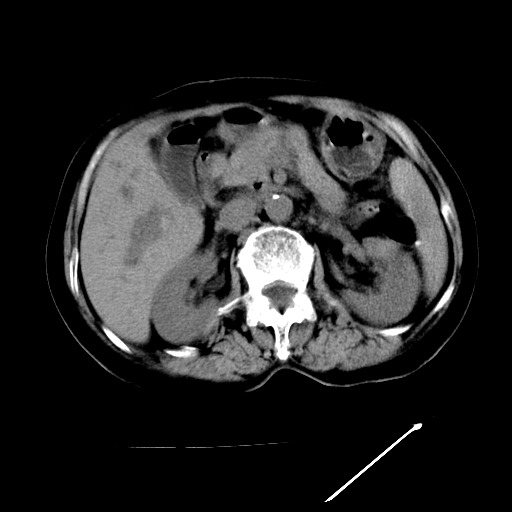

以下是引用卜一在2009-4-7 5:06:00的发言:[br]左右肝内胆管结石伴扩张合并胆系感染;不除外胆管细胞癌可能。支持! [br] [br]

以下是引用随光逐影在2009-4-7 8:21:00的发言:[br]肝内外胆管多发性结石并肝内外胆管扩张;胆系感染。